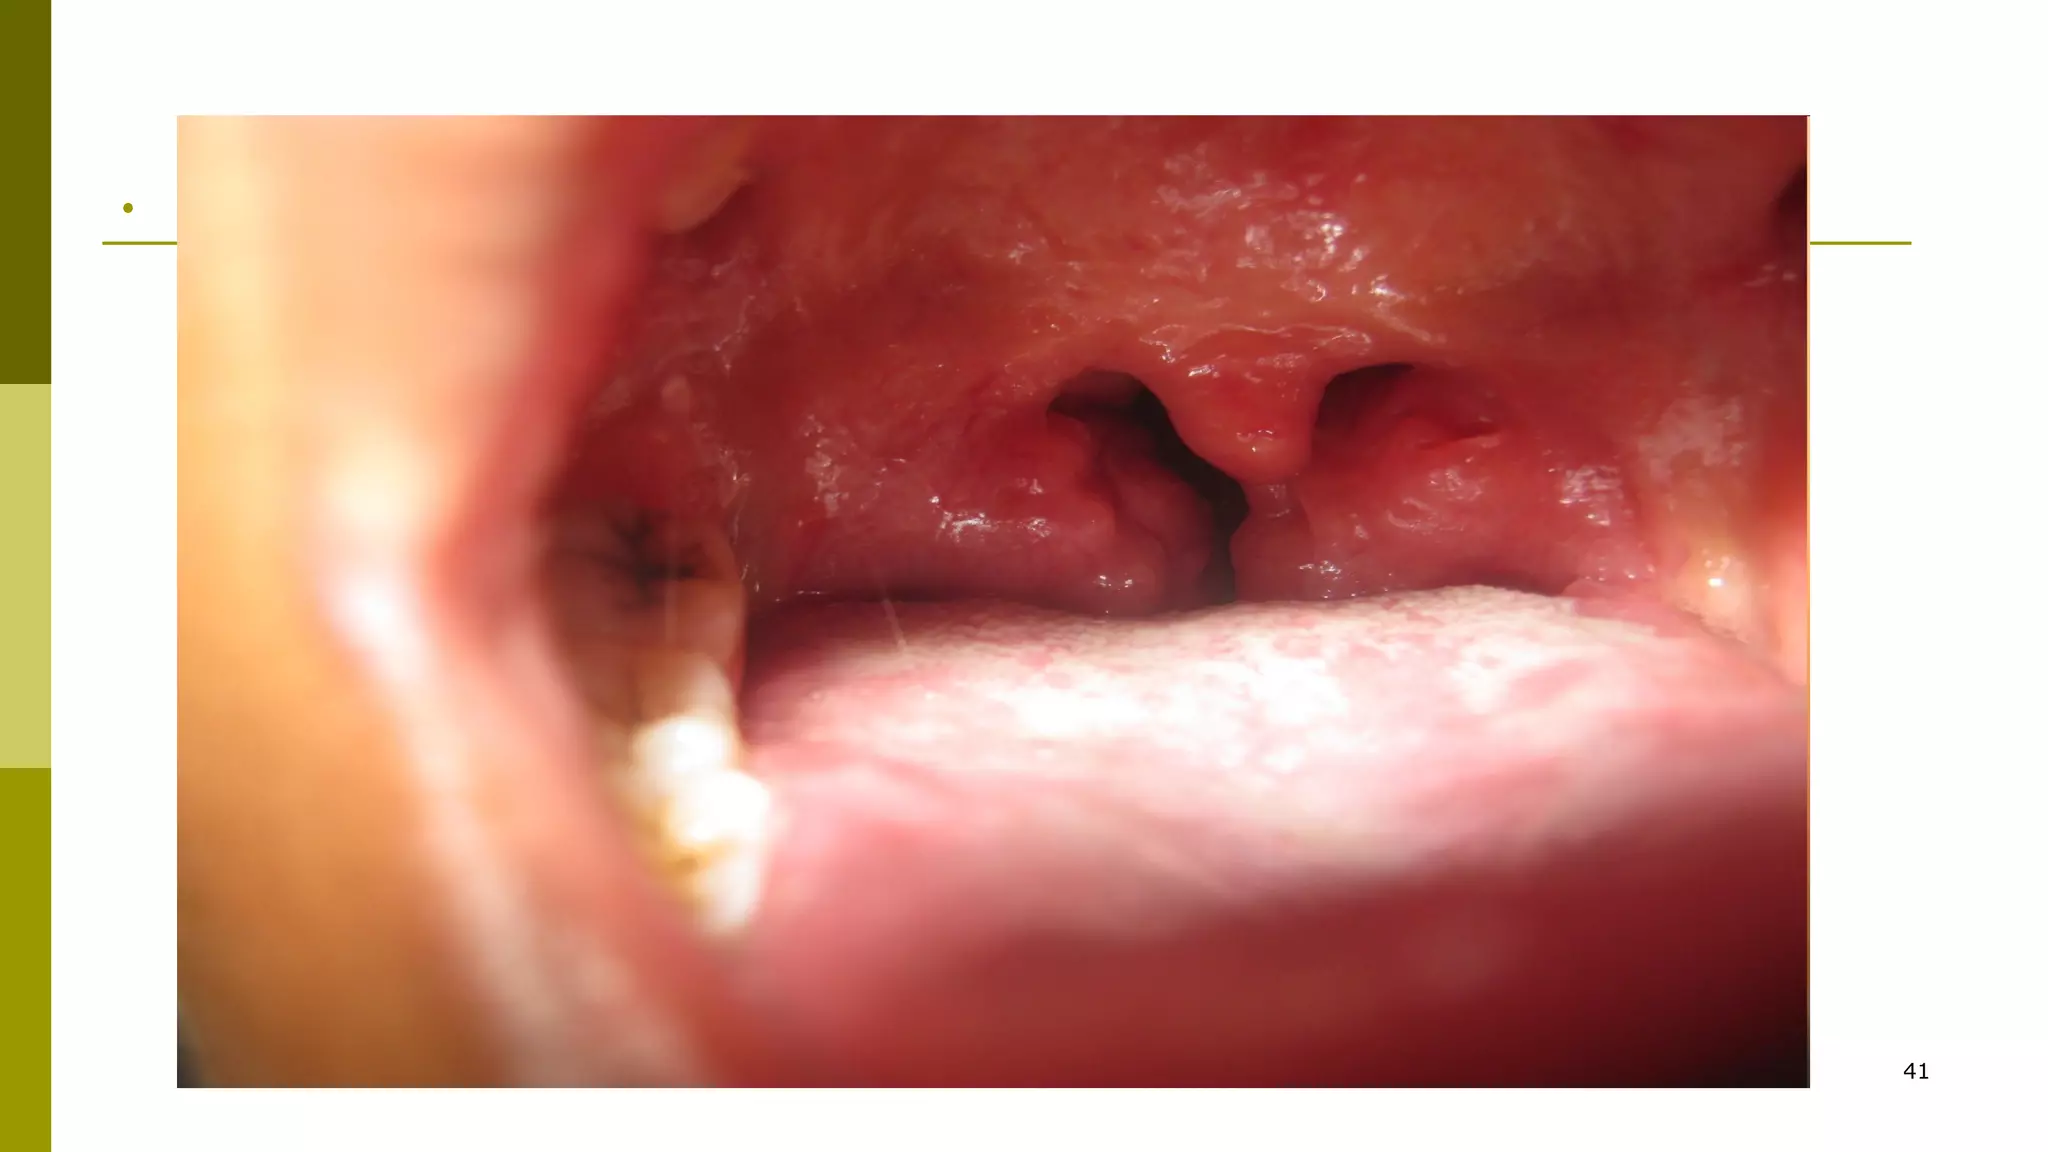

Tonsil in this pt were so swollen that they caused

resp distress necessitating tonsillectomy

Palatine tonsil which are bright red,swollen and

coated

.

41